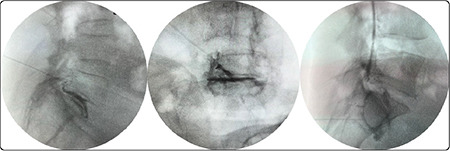

Objective: This study aimed to compare parasagittal interlaminar (PS) and transforaminal (TF) epidural steroid injections for unilateral L5 and S1 radicular lower back pain in terms of patient comfort, efficacy, safety, contrast enhancement, and radiation exposure.

Methods: This was a prospective randomized single-blind study. A total of 59 participants were included in this study. The visual analog scale (VAS) and Oswestry Disability Index (ODI) were obtained. A comfort questionnaire was administered to all participants. The total fluoroscopy time and contrast distribution levels were recorded.

Results: Pre- and post-treatment VAS scores were similar between the groups. The ODI scores increased in favor of the PS group at week 2 (P < 0.041); however, there was no difference between the two groups at other times. The VAS and ODI scores improved significantly with treatment in both the groups (P < 0.001). Total fluoroscopy time was shorter in the PS group (P < 0.001). PS application was more comfortable (P < 0.001). While no complications were observed in the PS group, three complications occurred in the TF group. Anterior epidural contrast spread to three or more levels was observed in 57% of the participants in the PS group, whereas no spread to more than two levels was observed in the TF group.

Conclusion: The PS epidural approach is superior to the TF approach in terms of a low incidence of side effects, less radiation exposure, better patient comfort, higher epidural contrast spread, and single-level needle access.